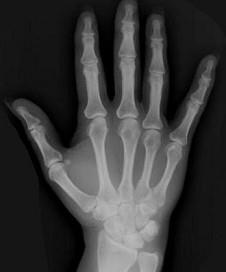

问题 女,41岁,纺织工,腕部痛无力数周,请结合CR和MR,选出最可能的诊断 ( )

选项 A、骨髓炎 B、骨软骨炎 C、月骨缺血坏死 D、骨质疏松 E、月骨结核

答案 C